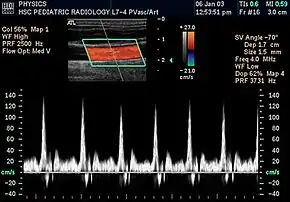

%252C_diastolic_velocity_(Vd)%252C_acceleration_time_(AoAT)%252C_systolic_acceleration_(Ao_Accel)_and_resistive_index_(RI)_of_normal_kidney.jpg.webp)

Doppler ultrasonography is widely used in renal ultrasonography. Renal vessels are easily depicted by the color Doppler technique in order to evaluate perfusion. Applying spectral Doppler to the renal artery and selected interlobular arteries, peak systolic velocities, resistive index, and acceleration curves can be estimated (Figure 4) (e.g., peak systolic velocity of the renal artery above 180 cm/s is a predictor of renal artery stenosis of more than 60%, and a resistive index, which is a calculated from peak systolic and end systolic velocity, above 0.70 is indicative of abnormal renovascular resistance).[12]